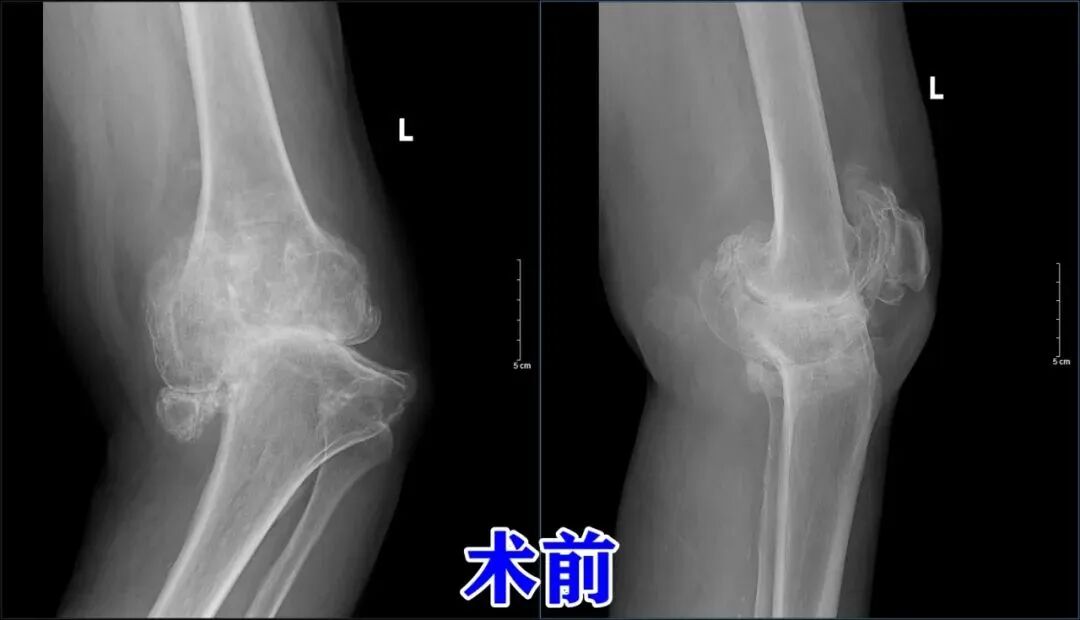

门诊李守斌主任接诊后经过详细地查体,结合影像学资料,患者左膝关节明显肿胀,内翻畸形严重,应力位左膝内翻竟高达48度,力线严重偏曲,确诊为“左膝关节骨性关节炎伴内翻畸形”。遂收入院。鉴于患者家庭经济条件有限,济南南郊医院高伟副院长代表济南市一粒种子公益基金会为患者送来关爱,嘱托患者安心治疗,在痊愈后医院与基金会将会给予很大的帮助。

在手术室和麻醉科团队的密切配合下,由骨一科郭云财主任主刀,顺利为患者实施手术治疗。术中见患者左膝关节所有关节面磨损严重,软骨下骨裸露,股骨髁及胫骨平台周围骨质严重增生,股骨髁间增生骨赘已完全覆盖髁间窝,前后交叉韧带残端包裹其内,胫骨平台内侧部分骨质缺损,内侧副韧带挛缩,外侧副韧带极度松弛,内外侧半月板磨损、撕裂,关节内滑膜充血、肿胀、变性、坏死。手术难度,可想而知,但郭云财主任凭借丰富的手术经验和娴熟的技术,成功完成了此台手术。